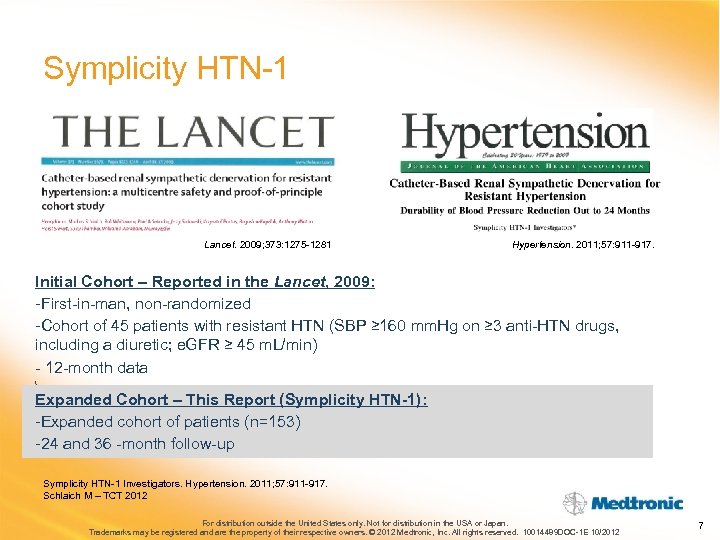

Symplicity HTN-1 Lancet. 2009; 373: 1275 -1281 Hypertension. 2011; 57: 911 -917. Initial Cohort – Reported in the Lancet, 2009: -First-in-man, non-randomized -Cohort of 45 patients with resistant HTN (SBP ≥ 160 mm. Hg on ≥ 3 anti-HTN drugs, including a diuretic; e. GFR ≥ 45 m. L/min) - 12 -month data Expanded Cohort – This Report (Symplicity HTN-1): -Expanded cohort of patients (n=153) -24 and 36 -month follow-up Symplicity HTN-1 Investigators. Hypertension. 2011; 57: 911 -917. Schlaich M – TCT 2012 For distribution outside the United States only. Not for distribution in the USA or Japan. Trademarks may be registered and are the property of their respective owners. © 2012 Medtronic, Inc. All rights reserved. 10014489 DOC-1 E 10/2012 7

Symplicity HTN-1 Lancet. 2009; 373: 1275 -1281 Hypertension. 2011; 57: 911 -917. Initial Cohort – Reported in the Lancet, 2009: -First-in-man, non-randomized -Cohort of 45 patients with resistant HTN (SBP ≥ 160 mm. Hg on ≥ 3 anti-HTN drugs, including a diuretic; e. GFR ≥ 45 m. L/min) - 12 -month data Expanded Cohort – This Report (Symplicity HTN-1): -Expanded cohort of patients (n=153) -24 and 36 -month follow-up Symplicity HTN-1 Investigators. Hypertension. 2011; 57: 911 -917. Schlaich M – TCT 2012 For distribution outside the United States only. Not for distribution in the USA or Japan. Trademarks may be registered and are the property of their respective owners. © 2012 Medtronic, Inc. All rights reserved. 10014489 DOC-1 E 10/2012 7